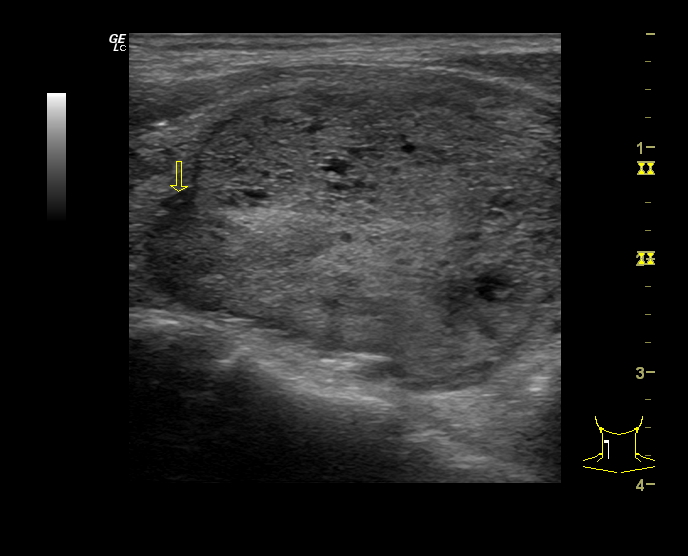

Hallazgos ecográficos

Se estudia la glándula tiroidea mediante sonda lineal de alta frecuencia, realizando cortes transversales y longitudinales. A nivel del lóbulo tiroideo derecho se objetiva un nódulo sólido, con forma «más ancho que alto», isoecoico, con zonas heteroecoicas de 2,4 x 3,4 cm (figura 1), que presenta una lobulación en su margen interno (figura 2), con halo periférico incompleto y vascularización mixta, principalmente periférica (figura 3). No se observan calcificaciones ni adenopatías patológicas. Adyacente al mismo, otro nódulo milimétrico (figura 4), de similares características.